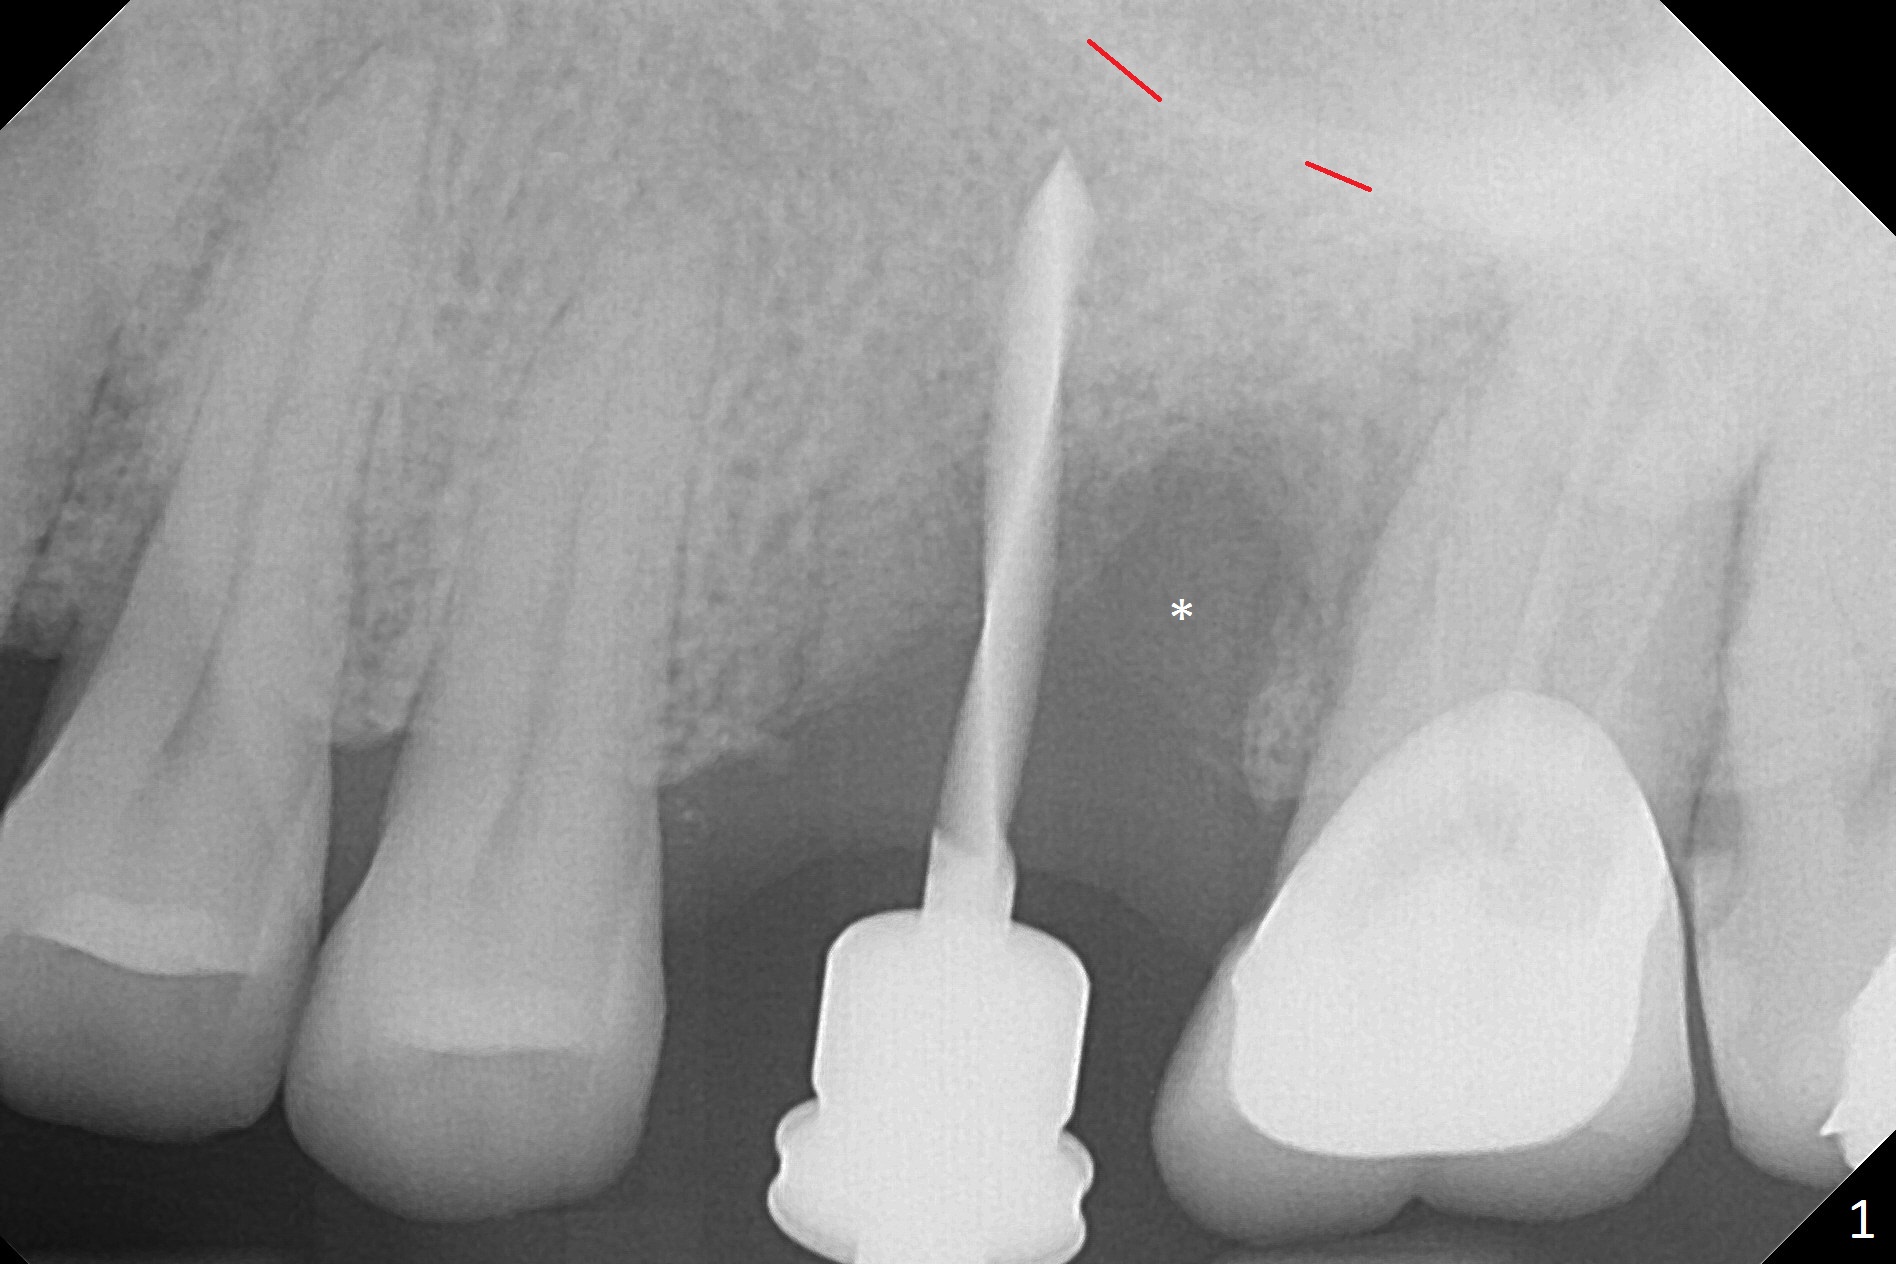

Magic Split is used to start access (flapless) and initial bone expansion at #14. The split does not go deep, since bone density is high in the deep portion. A 1.6 mm drill has to be used for 13 mm (Fig.1). Note the low bone density in the distobuccal socket (*). Later the osteotomy extends to 15 mm (gingival level). After 3.8 mm Magic Drill (MD) for 15 mm, a 4x11 mm dummy implant is placed with insertion torque of 60 Ncm (implant motor, Fig.2). After 4.3 mm MD, a 4.5x11 mm IBS implant is placed with insertion torque of 60 Ncm for implant motor >40 Ncm for torque wrench (Fig.3). The implant seems to be placed deep, but the buccal plate feels to be low. Following bone graft buccally, especially distobuccal (Fig.4,5 ^), a 5x4(3) mm abutment is placed. The buccal gingiva is torn during bone graft (Fig.6 >). Periodontal dressing is applied around the abutment (for increased retention) for wound protection.